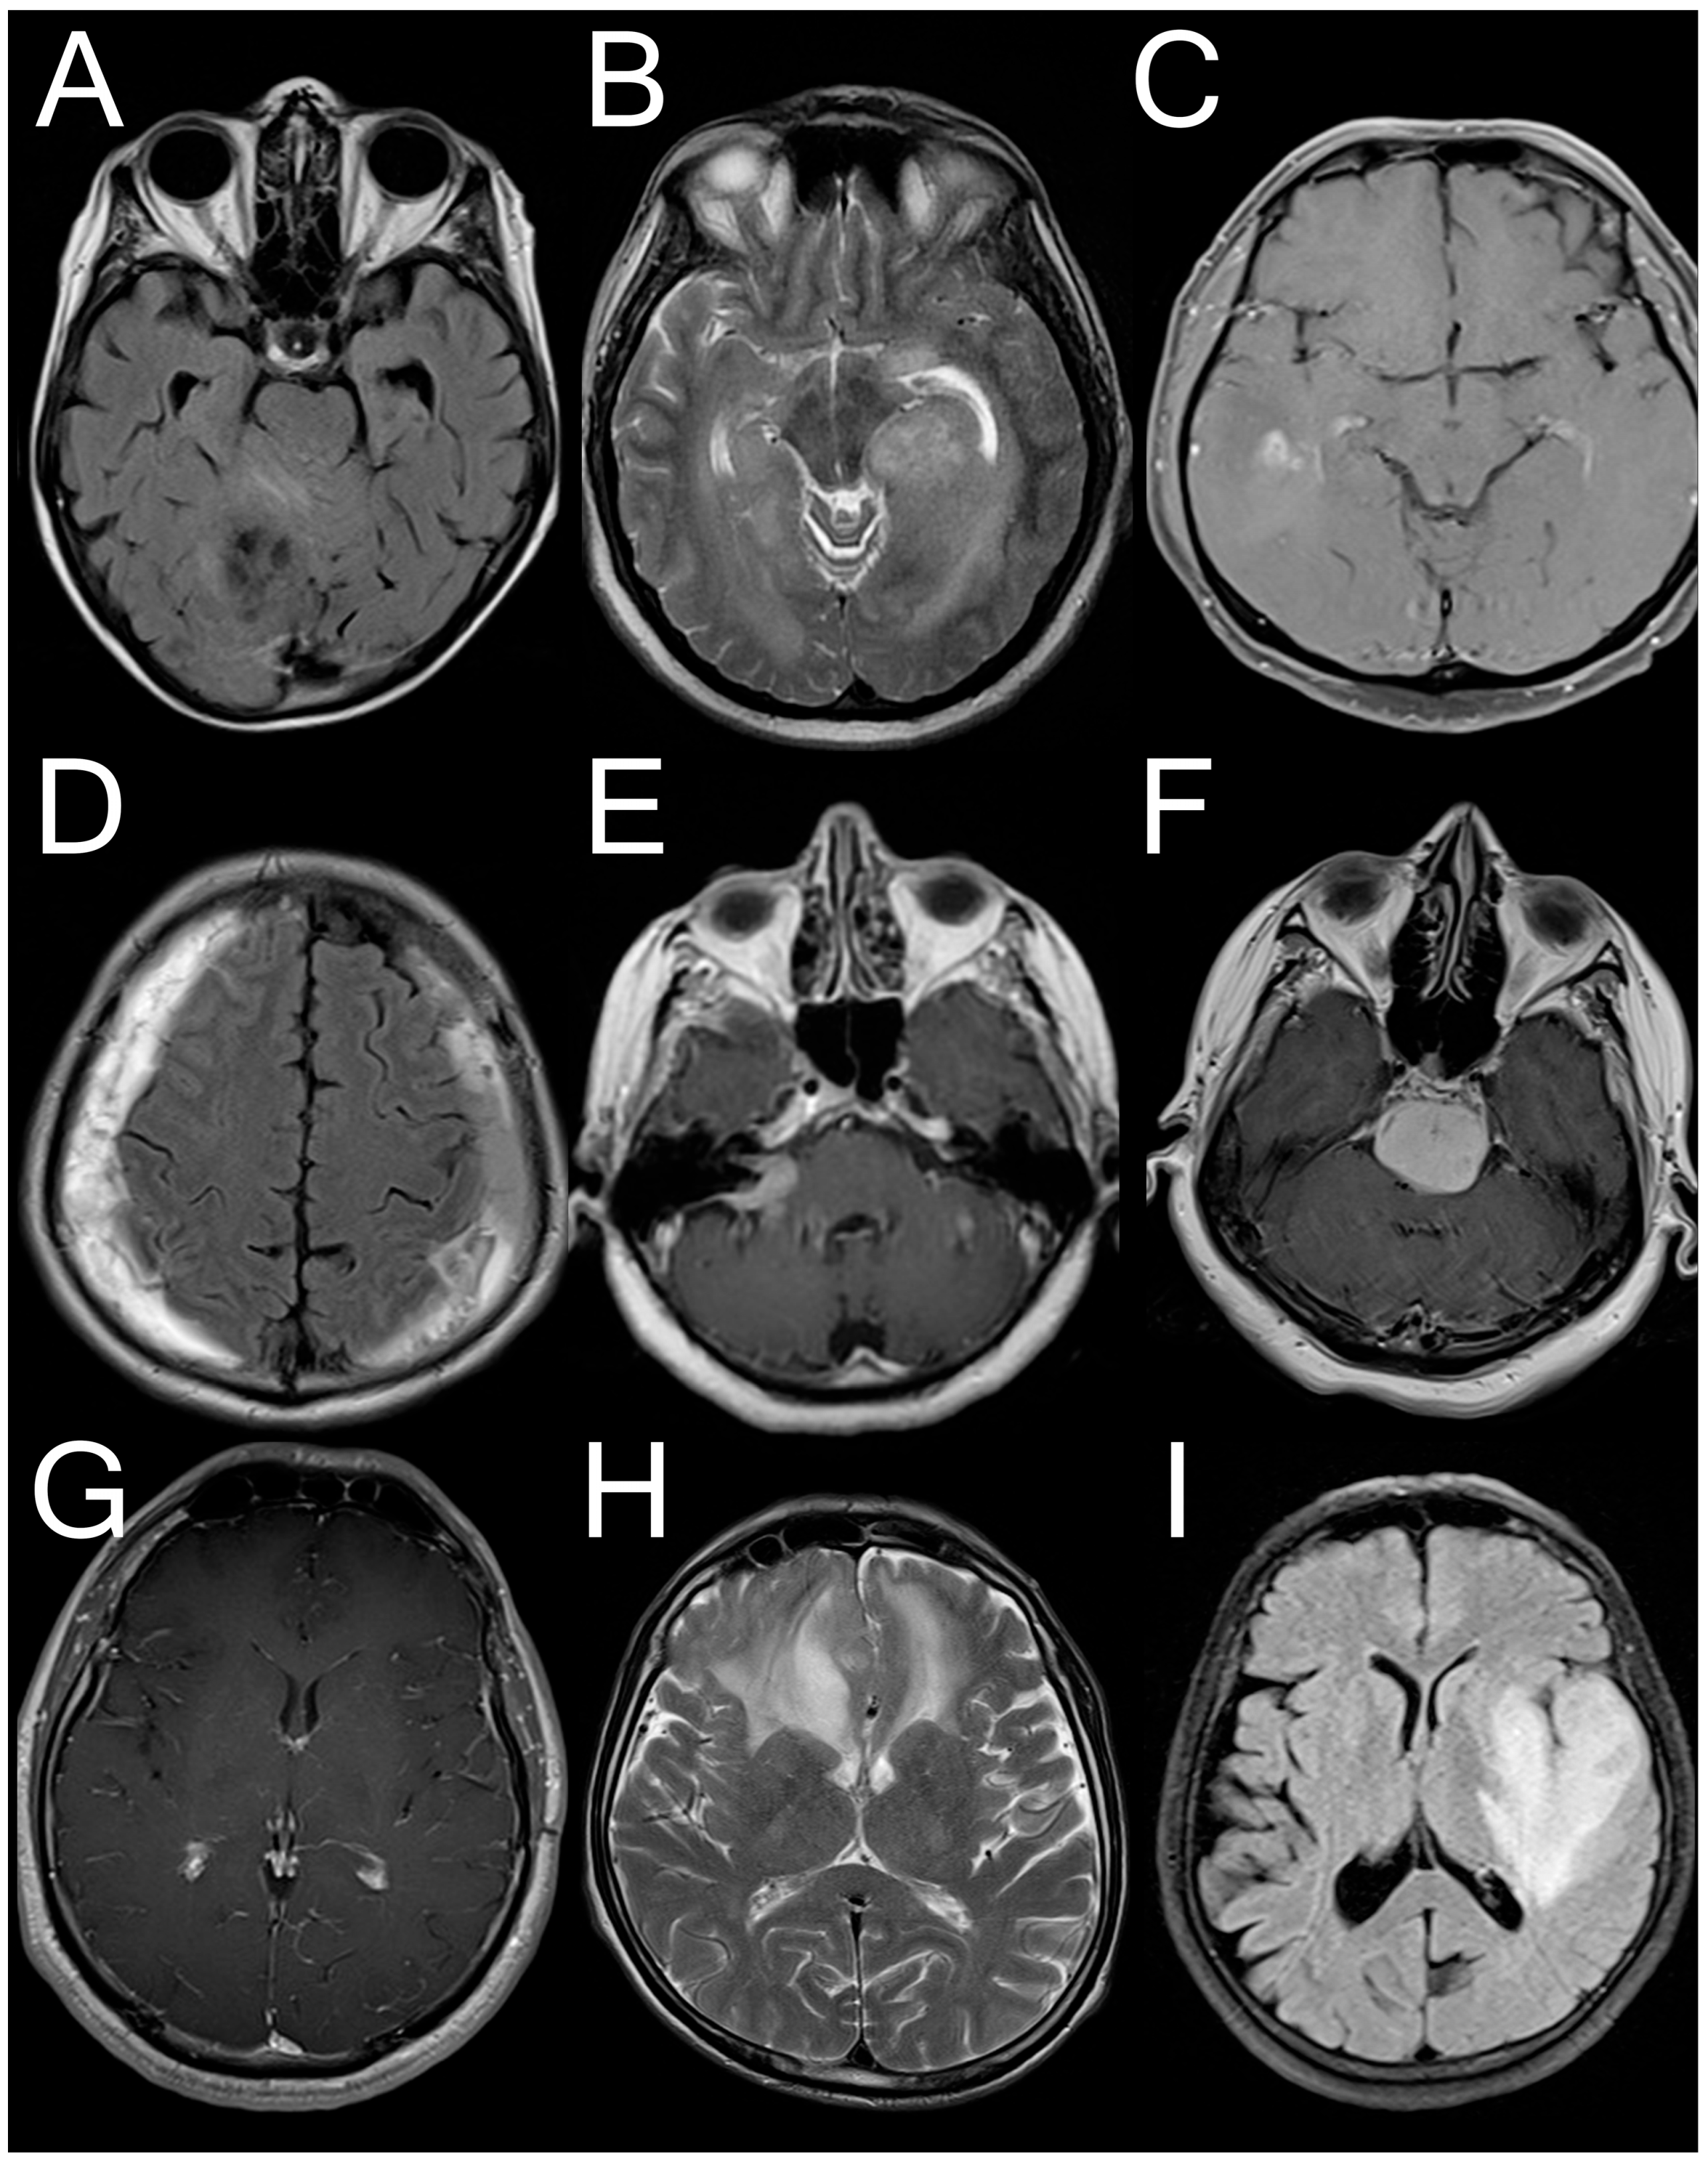

Figure A1. Sample images from the dataset that demonstrate some disagreement cases. TP: True Positive; FN: False Negative; FP: False Positive. (A): Only GPT TP; (B): Only Grok TP; (C): Only Gemini TP; (D): Only GPT FN; (E): Only Grok FN; (F): Only Gemini FN. (G): All FP; (H): All FN; (I): All TP.

None of the LLMs were able to correctly answer for 4975 (13.4%) slices, 11,482 (32.2%) were classified correctly by two LLMs at the same time, and 13.474 (37.7%) were correctly classified by all LLMs. Detailed distributions are presented in Figure 2. Representative MRI slices illustrating model predictions have been included as Appendix B to improve transparency.